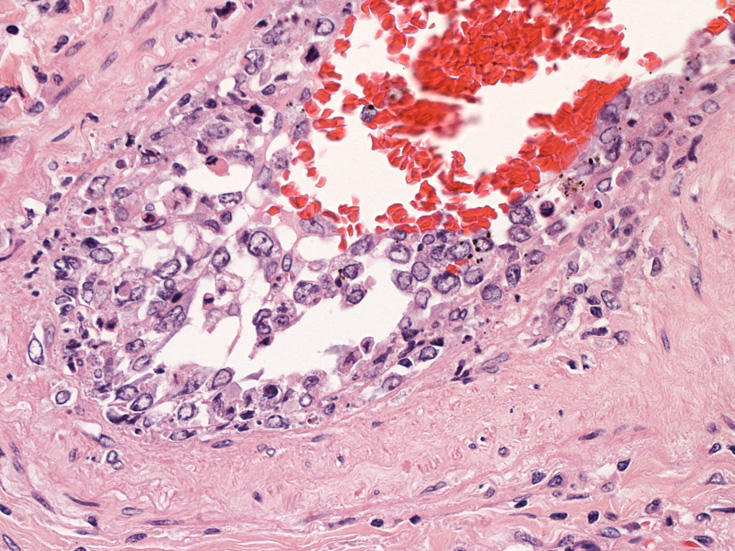

肺B;小気管支動脈, 肺動脈内を腫瘍細胞が閉塞する. 動脈内膜に浸潤性増殖している(B)。

脳;くも膜下腔の小動脈内, 脳白質の細血管内に腫瘍細胞が充満している。